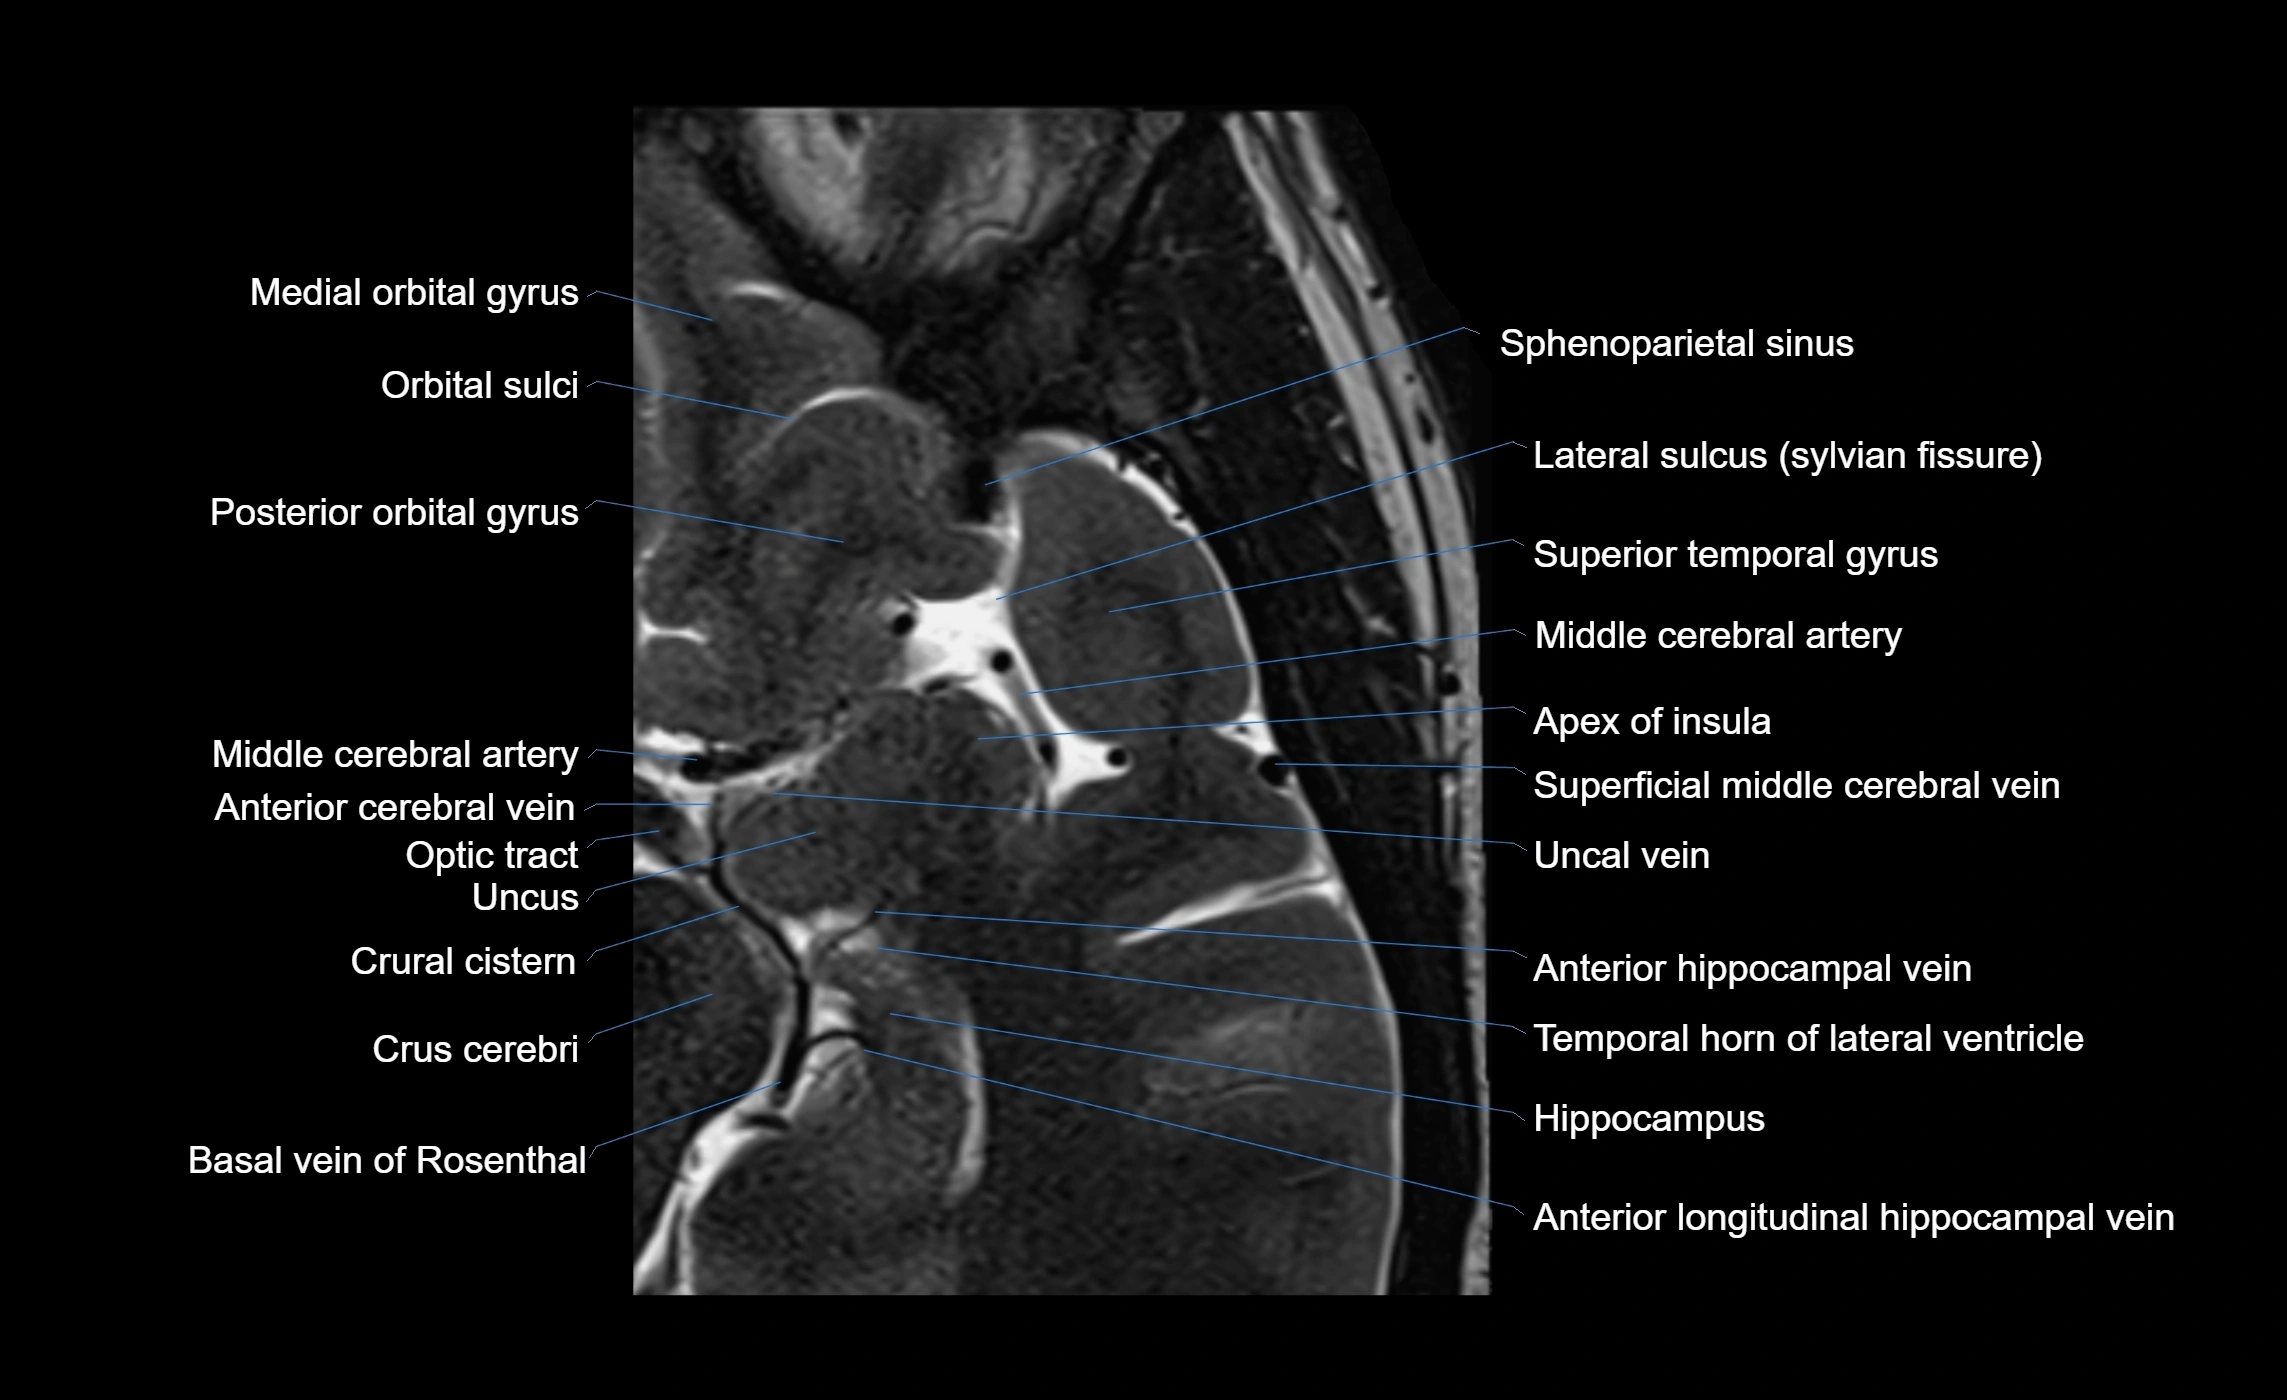

MRI Appearance

• T1-weighted imaging:

• The Sylvian fissure and its anterior ascending ramus appear as low-signal intensity (dark) CSF-filled clefts between the gyri.

• Clear demarcation between adjacent gray and white matter.

• T2-weighted imaging:

• The fissure, including the anterior ascending ramus, is hyperintense (bright) due to CSF signal.

• Better visualization of the separation between opercular and triangular parts of the inferior frontal gyrus.

Venous Drainage

• Drained by superficial Sylvian veins (also called superficial middle cerebral veins), which follow the course of the Sylvian fissure.

• Venous blood ultimately drains into the sphenoparietal sinus and cavernous sinus.

• Supplied predominantly by branches of the middle cerebral artery (MCA), particularly its opercular branches.

• The MCA runs within the Sylvian fissure and provides small cortical branches to adjacent gyri and sulci.